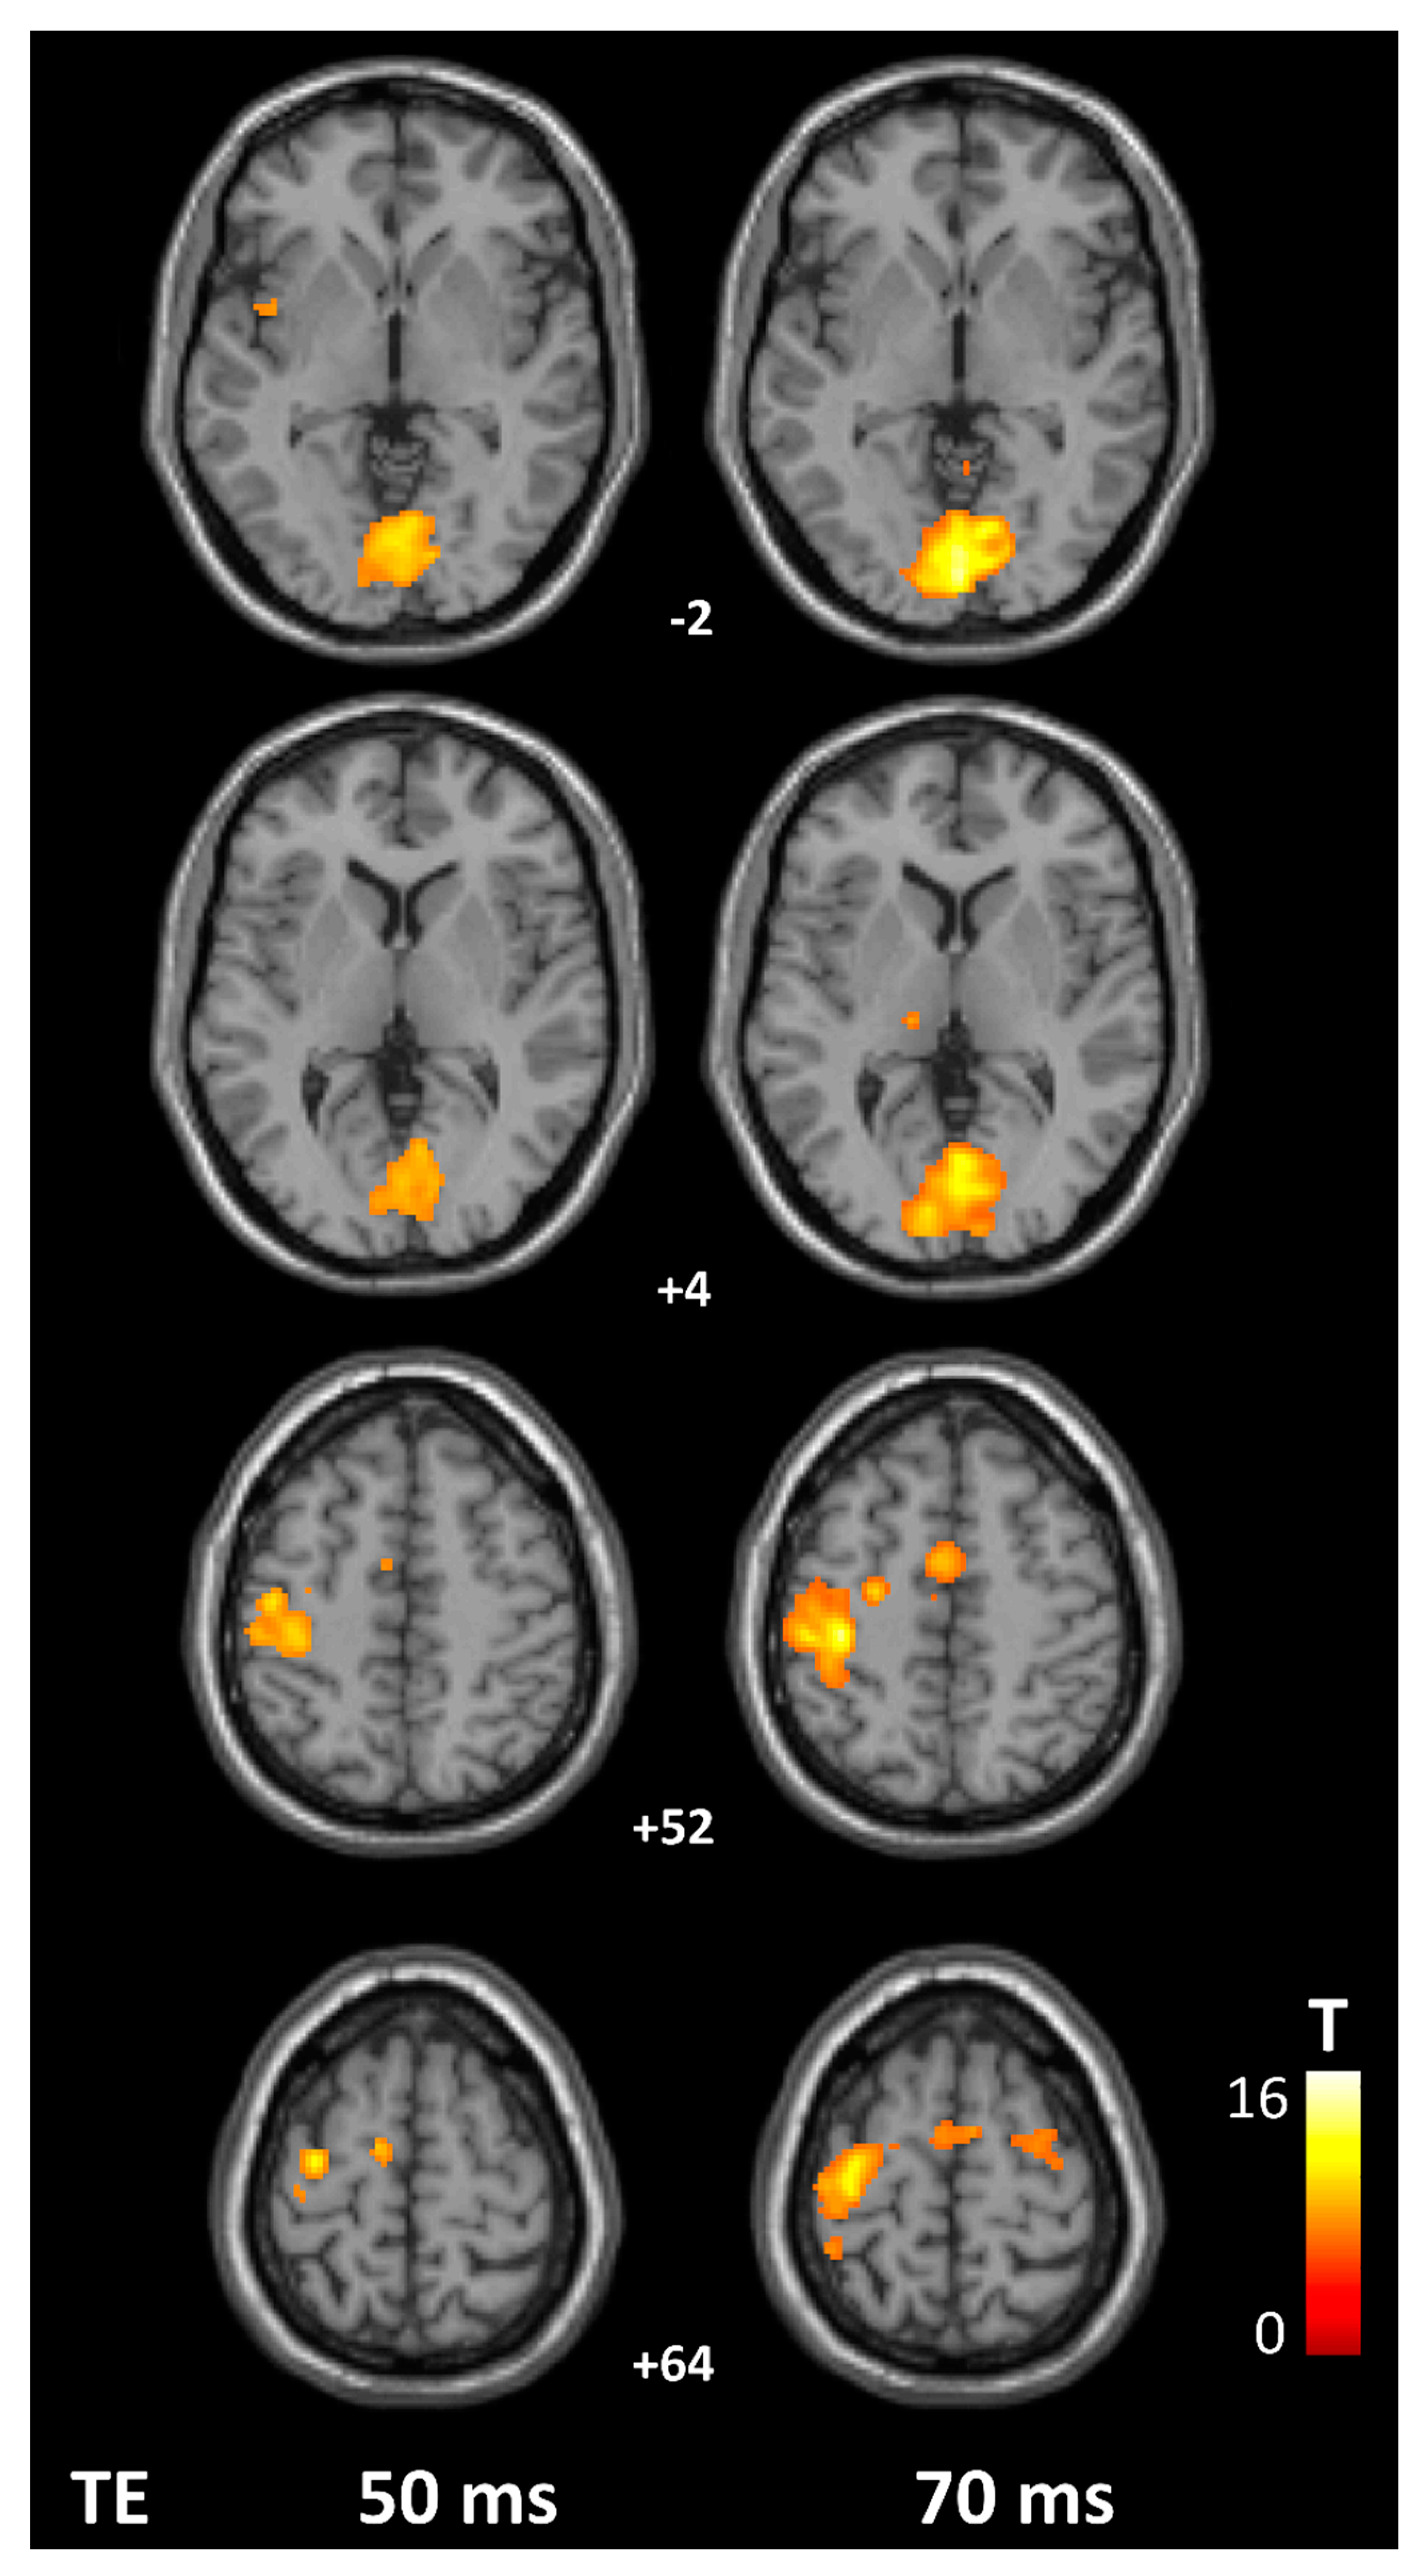

TE 50 ms | TE 70 ms | ||||

---|---|---|---|---|---|

Mean | SD | Mean | SD | p Value | |

Number of active voxels | |||||

MI (LH) | 529.3 | 380.4 | 735.9 | 341.8 | 0.002 |

PMd (LH) | 111.4 | 117.4 | 142.1 | 121.8 | 0.1 |

SMA | 415.1 | 390.7 | 606.3 | 409.9 | 0.003 |

SI (LH) | 744.2 | 598.3 | 946.5 | 634.1 | 0.007 |

V1 (RH) | 1356.5 | 824.8 | 1400.0 | 601.0 | 0.7 |

V2 (RH) | 977.9 | 568.7 | 1102.9 | 530.5 | 0.2 |

Peak beta value | |||||

MI (LH) | 1.82 | 1.06 | 3.40 | 1.30 | <0.001 |

PMd (LH) | 2.33 | 1.27 | 3.92 | 1.40 | <0.001 |

SMA | 2.24 | 1.06 | 3.53 | 1.36 | <0.001 |

SI (LH) | 2.15 | 1.08 | 3.84 | 1.42 | <0.001 |

V1 (RH) | 3.55 | 1.65 | 4.85 | 1.54 | <0.001 |

V2 (RH) | 3.18 | 1.87 | 4.61 | 1.66 | <0.001 |